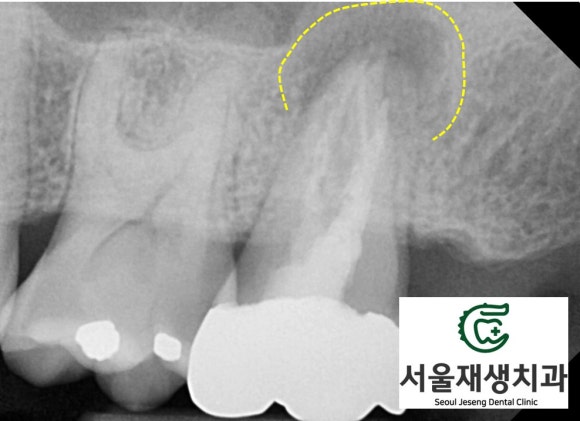

치아의 독사진을 촬영해봅니다.

단체사진보다 더 풍부하고 디테일한 정보를 줍니다.

일견 잘 되어 있는 치료처럼 보이지만,

밀도가 깊이가 부족해보입니다.

치아 내의 신경조직 잔사가 남아서 염증을 일으킨 것으로 보입니다.

극심한 통증과 치아가 흔들리는 증상까지 호소하셨습니다. 염증의 크기가 제법 클 것 같습니다.